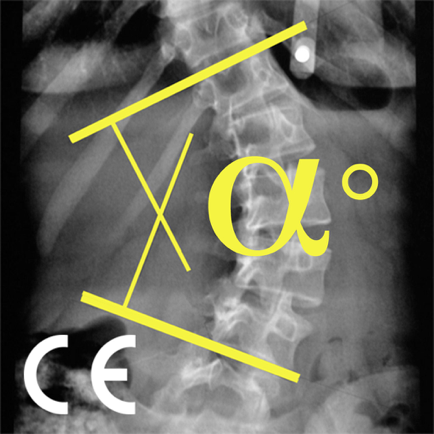

Regis RIGAL is a publisher of CobbMeter CE app.

CobbMeter CE

Medical |